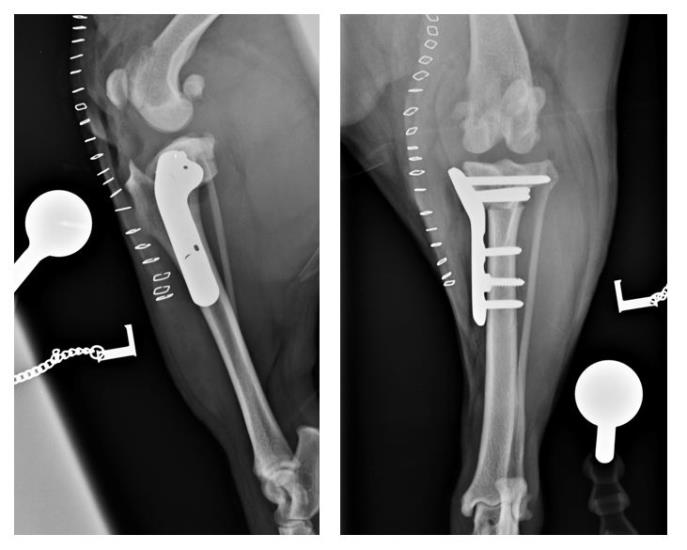

Treatment of concurrent Cranial Cruciate Ligament Rupture and Medial Patellar Luxation with a modified Tibial Plateau Levelling Osteotomy and Trochlear Block Recession in a Bulldog using an antimicrobial silver-coated bone plate.

To address the two conditions during a single anaesthetic event, a modified TPLO was carried out. This involves translating the entire distal fragment of the tibia laterally relative to the proximal fragment. This realigns the quadriceps mechanism without the need for a further osteotomy and the risks associated with it.

A trochlear block recession was also performed to further improve patella tracking within the femoral trochlea and minimise the risk of re-luxation.